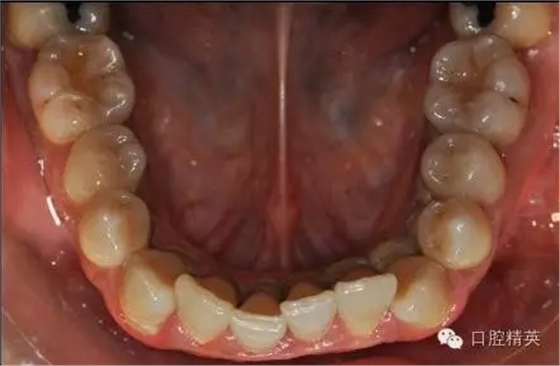

本病例 :女 34歲,主訴刷牙出血,覺牙齒輕度松動一年。

檢查見大量齦上及齦下結(jié)石,探診出血,牙周袋較深,32-42 II度松動。X線片顯示牙槽骨水平吸收。

診斷:成人慢性廣泛性中度牙周炎。

治療前: